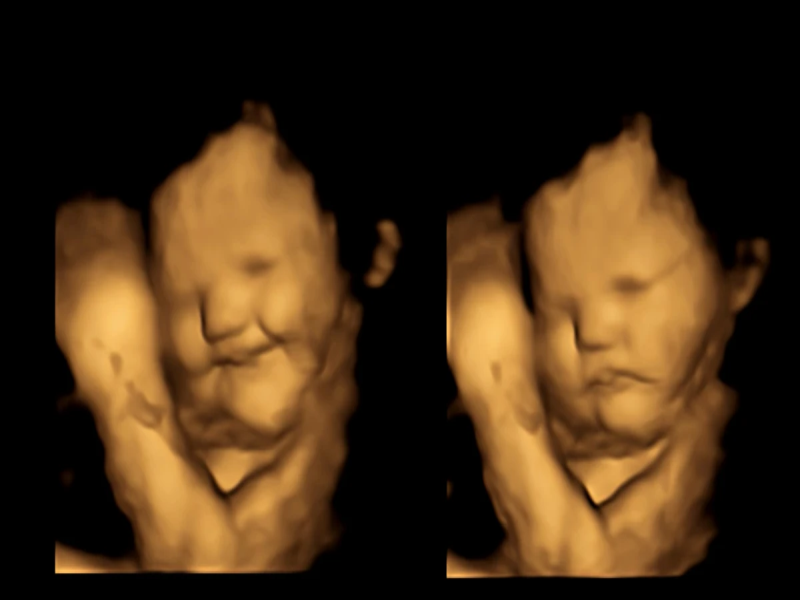

20 минути подоцна ултразвучните снимки покажале дека повеќето бебиња во утробата изложени на вкусот на кељ изгледаат како да прават гримаси, додека кога мајките јаделе морков, кај повеќето од нив била забележана насмевка на лицата. Контролната група ги немала истите одговори.

Сликите од ултразвукот покажуваат реакции слични на оние на децата или возрасните кога вкусуваат нешто горчливо, вели Рајсланд, но не е познато дали бебето навистина доживува емоции или не му се допаѓа на сличен начин.